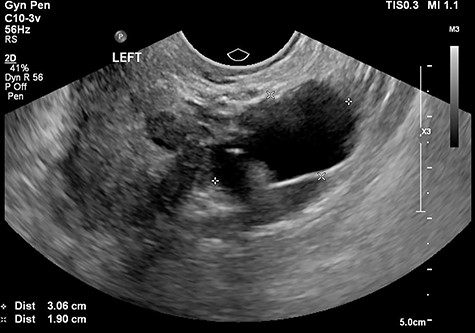

The tertiary ultrasound of the left adnexa demonstrating a 30 mm × 19 mm × 27 mm cystic structure with incomplete septae in keeping with a possible hydrosalpinx.

The tertiary level gynaecological ultrasound demonstrated a right adnexal serpiginous structure with a lumen and incomplete septae and a left adnexal cystic structure (Figs 1 and 2). The ultrasonographic features were consistent with those of hydrosalpinges [12]. The Ca125 remained negative. In view of the ultrasound diagnosis of hydrosalpinges and the patient’s post-menopausal status, a laparoscopic BSO was recommended and the patient subsequently consented.